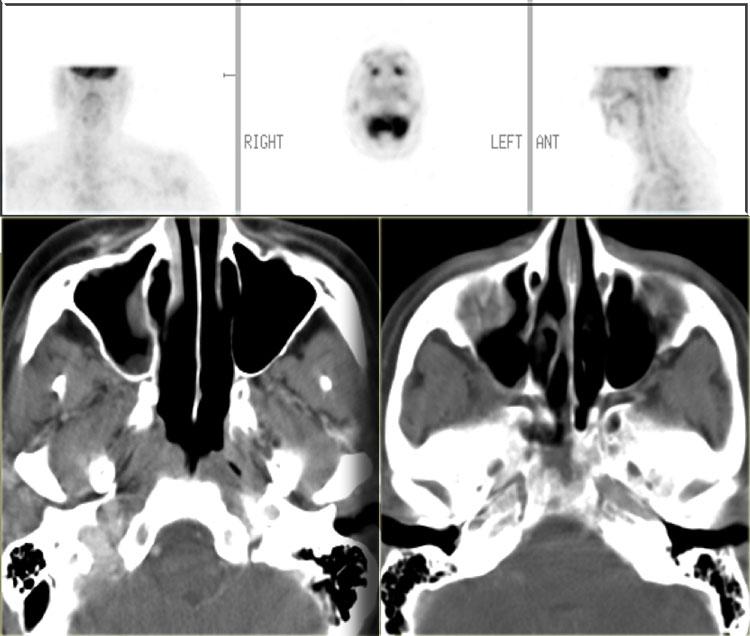

Theo dõi đáp ứng điều trị

Hình ảnh học cũng có thể được sử dụng để theo dõi đáp ứng điều trị.

Bệnh nhân này được chẩn đoán u lympho tế bào B tại nền sọ.

Trước điều trị, chúng ta thấy được mức độ lan rộng của tổn thương, với hình ảnh tăng hấp thu FDG.

Sau ba tháng điều trị, khối u tại nền sọ đã thoái lui hoàn toàn.

Không còn ghi nhận hình ảnh tăng hấp thu FDG bệnh lý, đồng thời có hiện tượng tái khoáng hóa xương.

Bệnh nhân bên trái đã được phẫu thuật cắt bỏ ung thư biểu mô.

Hiện tại ghi nhận tình trạng tái phát (mũi tên xanh lam trên ảnh MRI và ảnh hợp nhất).

Tuy nhiên, mũi tên xanh lá chỉ vào các thay đổi mô sau xạ trị.